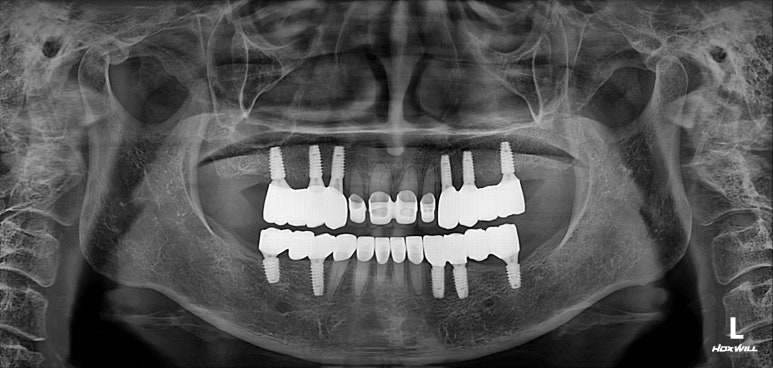

엑스레이는 지난 내원 때 찍었던 것인데, 한가지 알 수 있는 것은?

다행히도 잇몸뼈가 건강하고 많아서 충분히 임플란트로 치료가 가능하다는 것!!

엑스레이 또한 빼놓을 수 없죠!!

적절한 위치에 심어진 임플란트는 곧 적절한 임플란트 크라운으로 이어지게 되고,

당연히 모양도 예쁘게 제작되겠지만, 음식물이 끼는 것도 최소화됩니다.